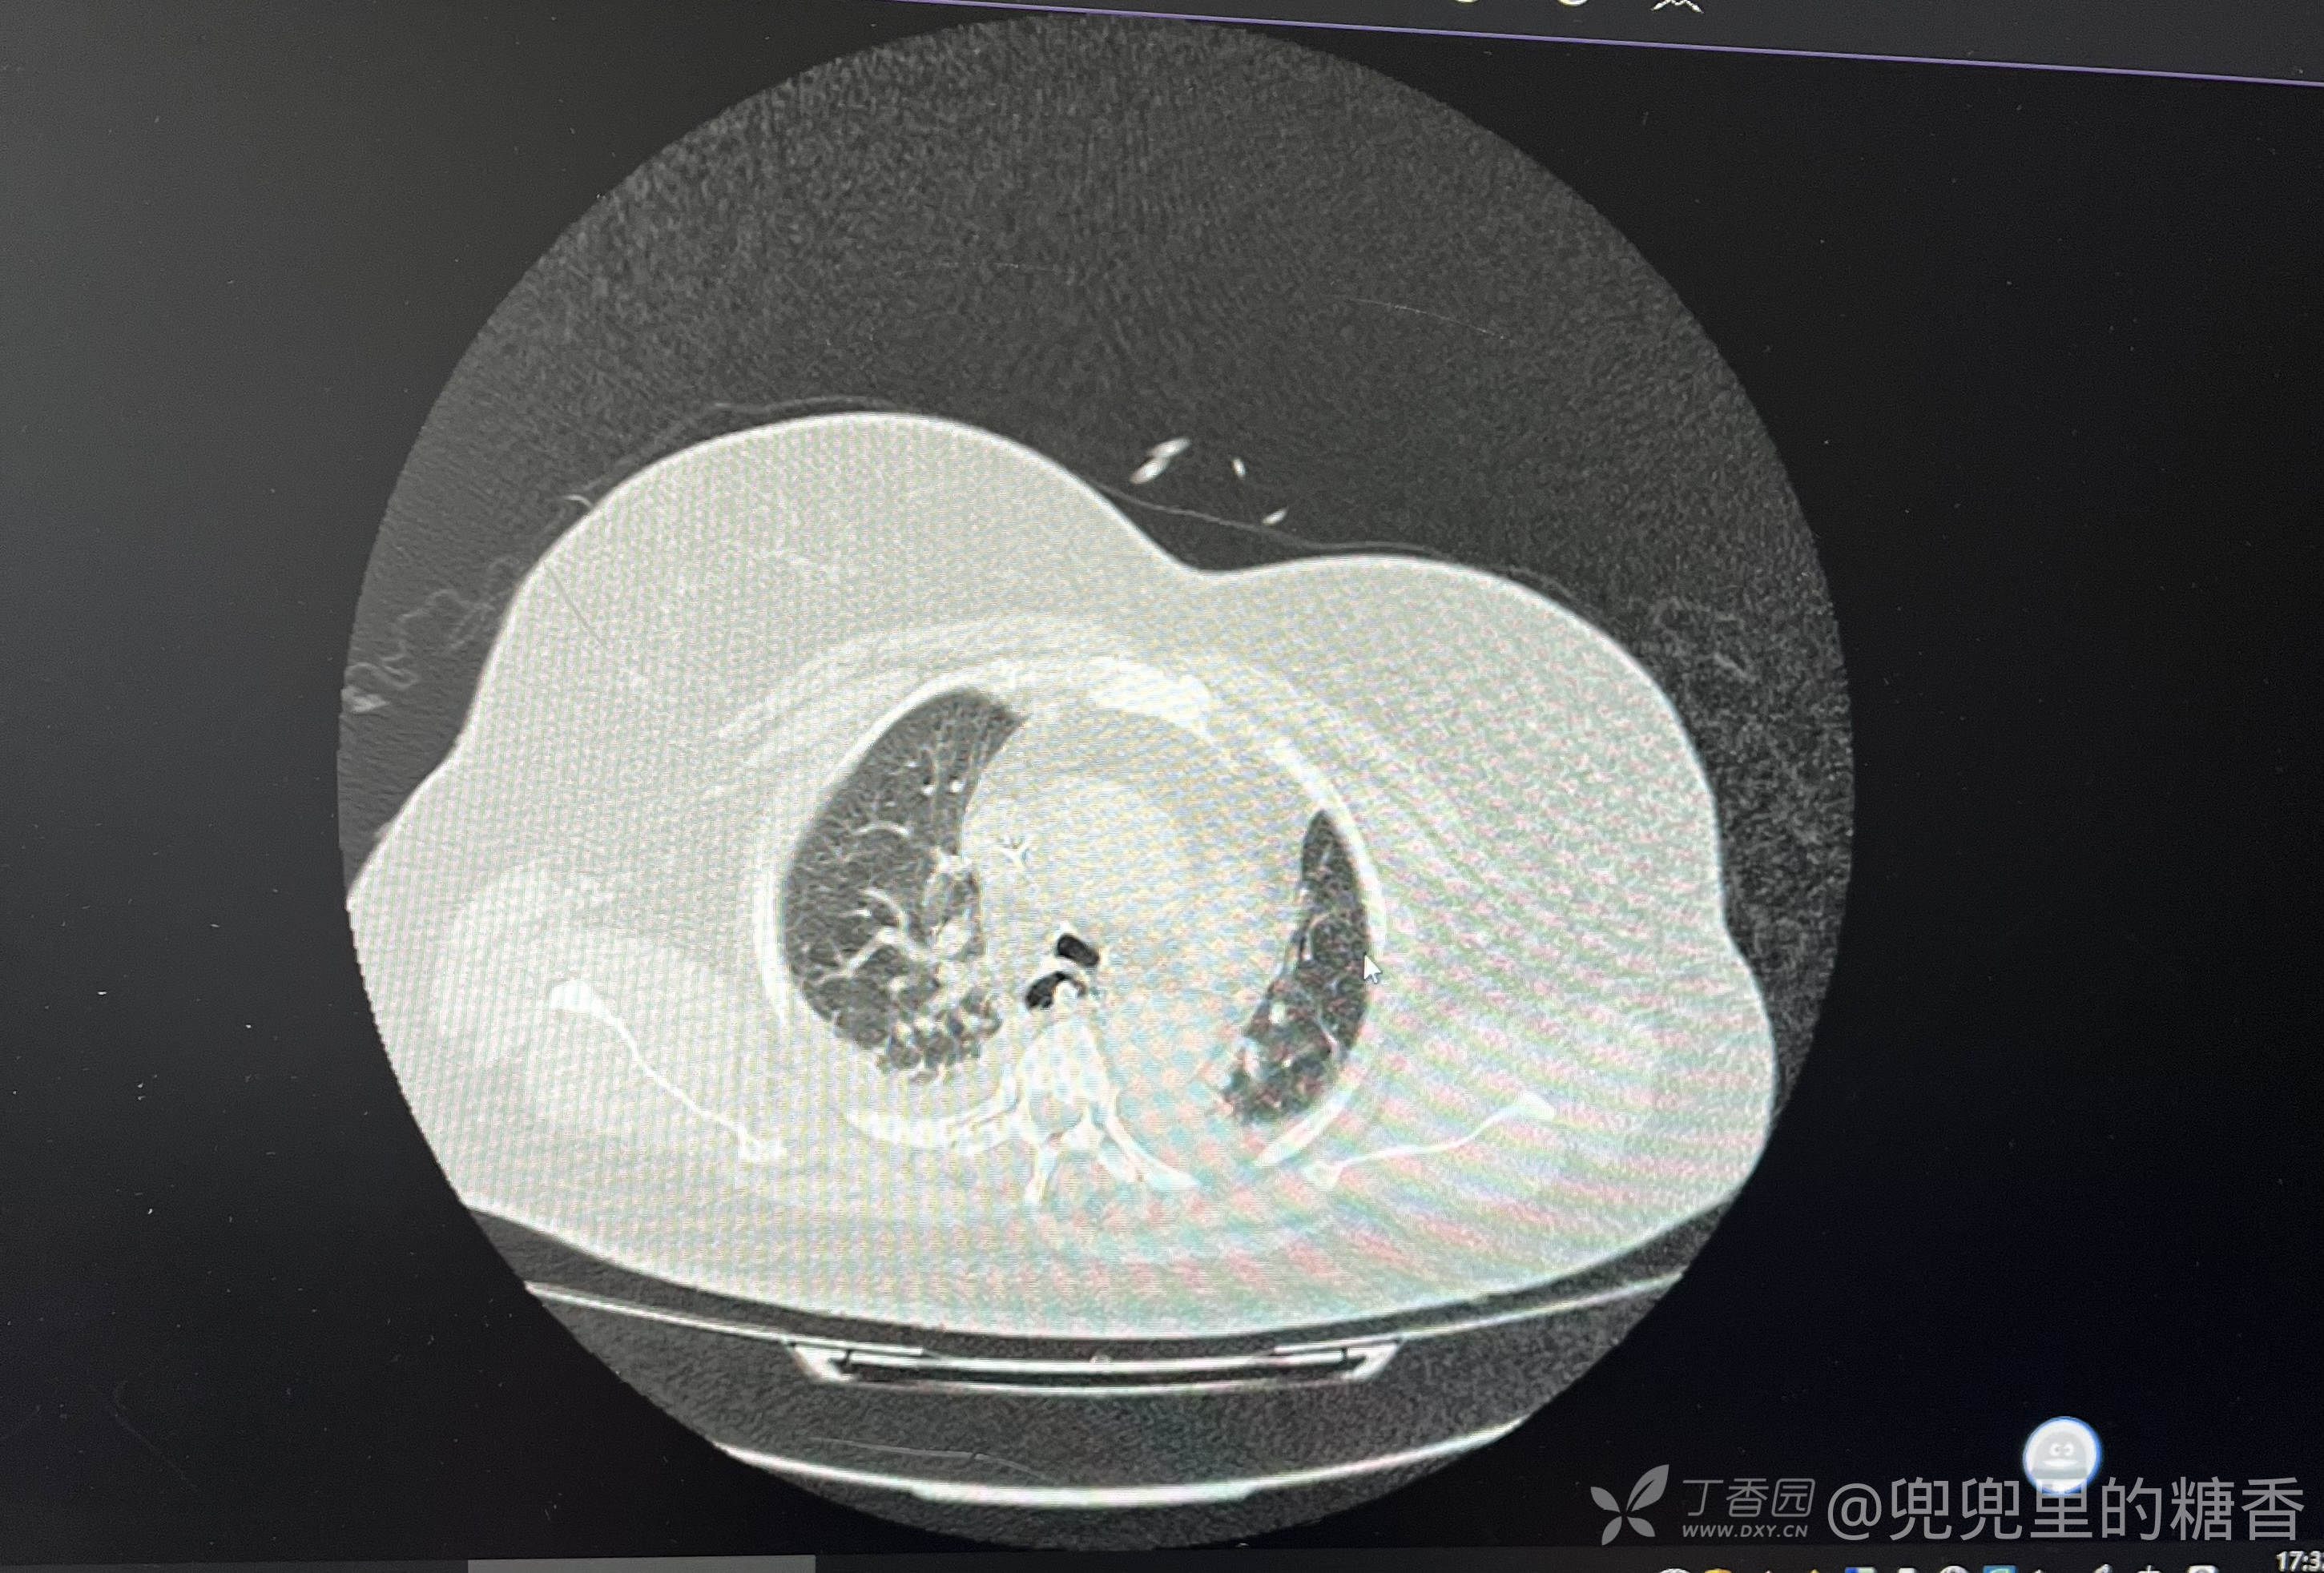

患者肥胖症,106公斤,近2月来体重增加10公斤,既往高血压病史15年,半月前出现乏力,加重一天入院。入院前一晚上出现意识障碍,入院是全身体浮肿,浅昏迷,吸氧10升/L,血氧饱和度80%,血压155/90mmHg,院外肺部CT提示肺部炎症,心脏扩大,考虑高心病并心力衰竭,呼吸衰竭,肺部感染